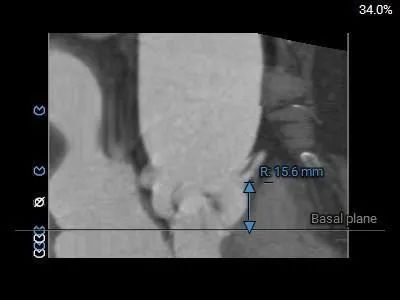

主动脉根部测量:

Type 0型二叶式主动脉瓣,瓣叶增厚,未见明显钙化,交界处未见明显融合